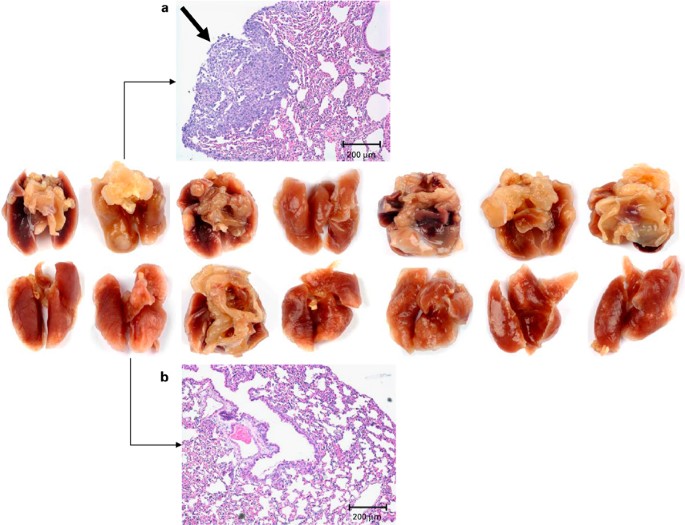

BMT (‘ in vivo ’ purging). A range of doses from 6.5 to 7.5 Gy for TBI was examined to find an optimal irradiation dose for HAL-based photodynamic purging. Total-body doses of 7 Gy and lower were sublethal with animals surviving without any sign of the disease for several months after γ-irradiation. Although γ-irradiation at a dose of 7.5 Gy resulted in death of all animals with median survival time of 15 days (11–15, n=5), a higher dose of 8.0 Gy was used for the TBI in in vivo experiments to ensure a sufficient dose to be delivered. BM was harvested from the donors injected s.c. with 0.5 × 106 4T1 cells 30–35 days before. The purging procedure consisted of 4-h incubation of BM contaminated with 4T1 cells in serum-free medium with 50 μM HAL followed by 120-s illumination with light. Two criteria were used to judge the outcome of the photodynamic purging, namely animal survival and number of pulmonary metastases. i.v. injection of 2 × 107 cells treated with the purging procedure into lethally irradiated animals without 4T1 tumor (recipients) resulted in the death of only one mouse (n=10) after 31 days (Figure 5), whereas 10 out of 12 recipient mice (in the control group) injected with the same amount of non-PDT-treated cells died within 16–29 days (Figure 5). Further, the pulmonary metastases in PDT-treated and non-PDT-treated animals were inspected. In one set of experiments, substantially lower numbers of metastases in the thoracic cavity (lung and mediastinum) were found in six out of seven surviving recipients than those in the control group (with one exceptional case) after 6 months (Figure 6). Histopathological findings confirmed the metastasized tumors in the lungs and their surrounding tissues (Figure 6). In the remaining set of experiments, no pulmonary metastases were found in any of PDT-treated animals.

Metastases in the thoracic cavity developed in the lethally irradiated BALB/c mice i.v. injected with PDT-treated (lower row) and non-PDT-treated (upper row) BM from the donors with metastasized 4T1 tumors. (a, b) Histopathology of 4T1 pulmonary metastasis. Transmission microphotographs of lung tissues of BALB/c mice i.v. injected with non-PDT-treated (a) and PDT-treated (b) BM from the donors with metastasized 4T1 tumors. The arrow in (a) shows a metastasized tumor.